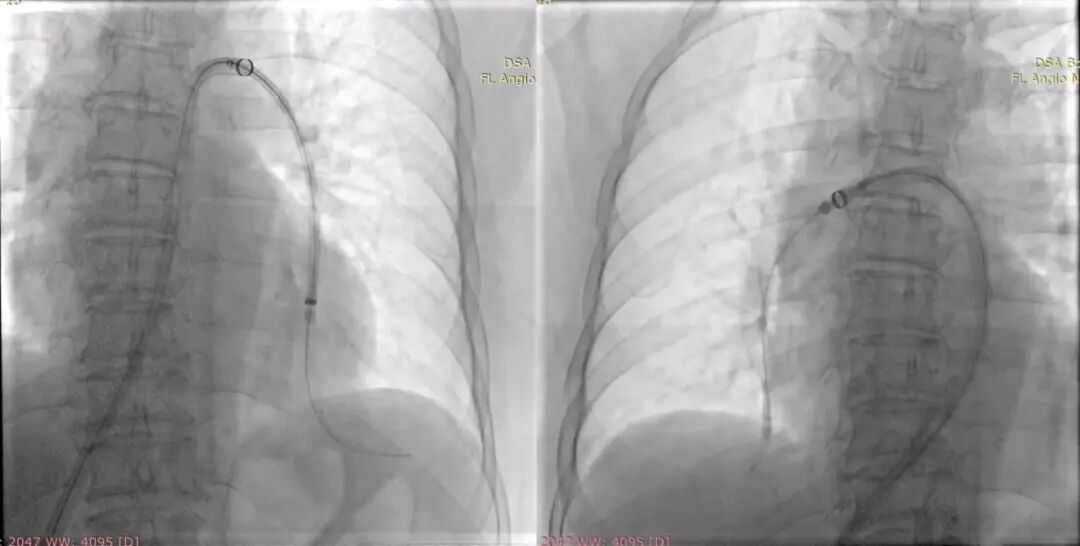

术后

全程手术时间不到1小时,患者术后生命体征平稳,氧饱和度上升至95%,胸闷不适症状减轻,手术成功,安返病房。